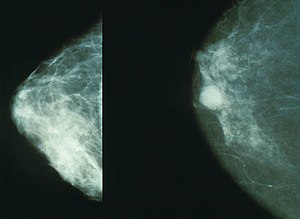

전 세계 여성 3명 중 1명이 암에 걸린다고 알려진 유방암에 좋은 음식과 유방암에 나쁜 음식에 대해서 살펴보도록 하겠습니다. 유방암은 갑상선암에 이어 여성에게 두 번째로 흔한 암이며, 중년 여성의 암 사망률 1위입니다.

유방암은 유방에서 발생하는 모든 악성 종양의 그룹이라고 합니다. 유방암은 유방의 비정상적인 조직이 계속 자라거나 다른 장기로 퍼지는 위험한 질병이라고 합니다. 가장 두드러진 원인은 DNA 손상 및 유전자 돌연변이와 같은 유전적 조건입니다.